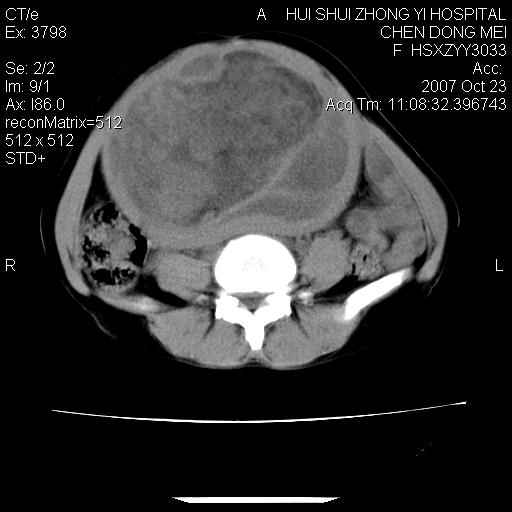

标题: CT10156:女.43岁,发现中下腹部包都块2年 [打印本页]

标题: CT10156:女.43岁,发现中下腹部包都块2年

发现中下腹部包都块2年。2年来月经不规律。

腹腔巨大软组织密度影,边缘光滑,包膜完整,内囊变坏死。腹膜后及盆腔内淋巴结肿大。结合病史考虑卵巢癌可能性大。

病变巨大,呈囊实性改变,包膜较厚且完整,内见分膈,周围脏器明显受压移位,病变与左侧附件关系密切,考虑来源左侧附件的囊腺瘤,不除外癌变可能;畸胎瘤可能性较小。

病变巨大,呈囊实性改变,包膜较厚且完整,内见分膈,周围脏器明显受压移位,病变与左侧附件关系密切,考虑来源左侧附件的囊腺瘤,盆腔内见肿大淋巴结,不除外癌变可能。

病变巨大,呈囊实性改变,包膜较厚且完整,内见分膈,周围脏器明显受压移位,病变与左侧附件关系密切,考虑来源左侧附件的囊腺瘤,不除外癌变可能